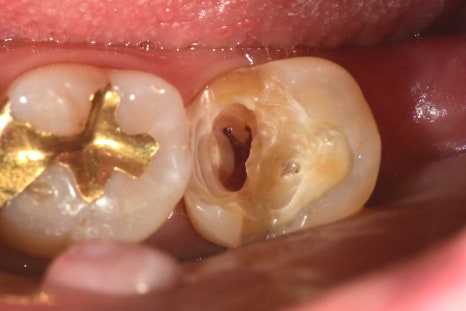

왼쪽 아래의 과거의 수복물이 탈락된 상태에서

방치된 상태에서 내원해 주셨습니다.

환자분께서는 신경치료를 받지 않고 치료해서 지내고 싶다고 하셨습니다.

오래된 접착제, 충치에 의해 영향받은 건강하지 못한 치질까지

제거를 모두 해주니 신경이 노출돼있었고

괴사되진 않았지만 노출 범위가 넓었고,

주변을 깨끗하게 소독하고 MTA를 사용해야 하기 때문에

노출된 신경 잔사를 마저 제거해 주고 지혈을 했습니다.

갈색빛이 나지만 건강한 치질이기 때문에 남겨놓은 상태로

소독, 지혈 후 적용

신경을 안정시켜주는 MTA는 강도가 약하기 때문에

그 상부로는 단단한 레진이라는 재료를 덮어줘

치아를 보강하고 그 위에 크라운 치료까지 마무리되었습니다.